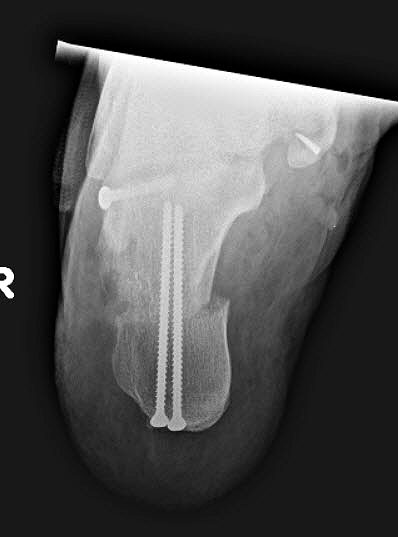

Stadium III – partielle Rückfuß-Arthrodesen

- In-situ / korrigierende USG-Arthrodese

Im Stadium III der Tibialis posterior Sehneninsuffizienz bei fixierter Deformität und/oder erheblich eingeschränkter Inversion im USG aber stabilen und flexiblen Chopart-Gelenk und weniger als 10° fixierter Vorfußsupination eine in-situ oder leicht korrigierende USG-Arthrodese indiziert. Der Vorteil einer isolierten USG-Arthrodese gegenüber einer Triple- oder Double-Arthrodese ist die verbleibende, funktionell wichtige Beweglichkeit in der Chopart-Gelenkreihe. Um einem persistierenden fibulocalcanearem Impingement sicher vorzubeugen, sollte die USG-Arthrodese in maximal 5° Valgus- oder sogar Neutralposition erfolgen. Zur Prophylaxe eines Rezidivs wird die USG-Arthrodese zudem häufig mit einer medialisierende Tuber calcanei Osteotomie und / oder einem FDL-Transfer kombiniert (Abb. 12).